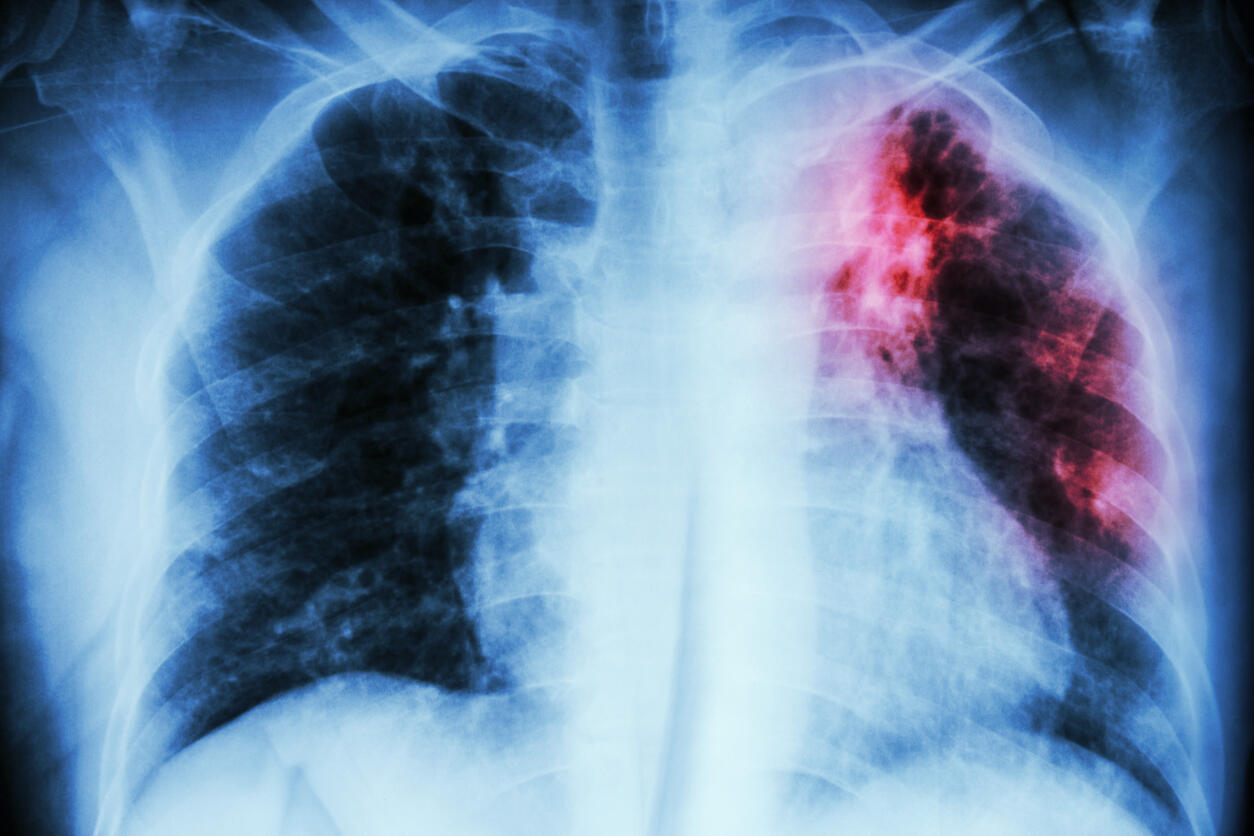

A new study aims to uncover whether TB causes long-term lung damage that affects people’s quality of life.

The initial small-scale research will examine the potential prevalence of post-TB lung disease, which has been identified in countries with a high TB burden. However, little is currently known about how common this is in the UK or other countries with lower rates of the disease.